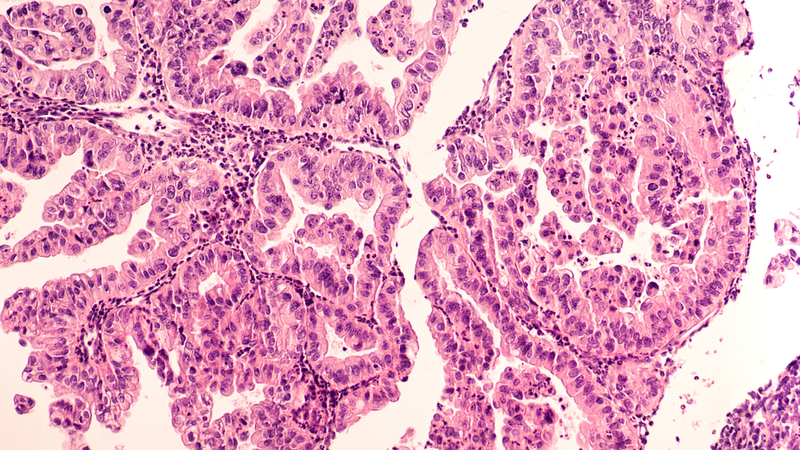

For the study, researchers used the software to identify the aggressiveness of tumours in CT scans and tissue samples from 364 women with ovarian cancer. The patients were then given a score known as Radiomic Prognostic Vector (RPV) which indicates how severe the disease is, ranging from mild to severe.